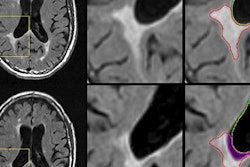

As one might expect, baseline resting-state fMRI showed that MS patients had significantly lower functional connectivity clusters in the cerebellum, frontal and occipital cortices, caudate nucleus, and thalamus than the healthy subjects.

Axial statistical maps show areas of reduced thalamic functional connectivity in patients with MS compared with healthy subjects. Patients exhibited significantly lower functional connectivity in clusters located in the cerebellum, frontal and occipital cortices, caudate nucleus, and thalamus, bilaterally. Image courtesy of Radiology.However, there was no significant difference in baseline functional connectivity maps of the thalamic resting-state network between the waitlist and intervention groups. The scans covered the cerebellum, thalamus, basal ganglia, and cingulate, frontal, temporal, occipital, and bilateral parietal cortices.